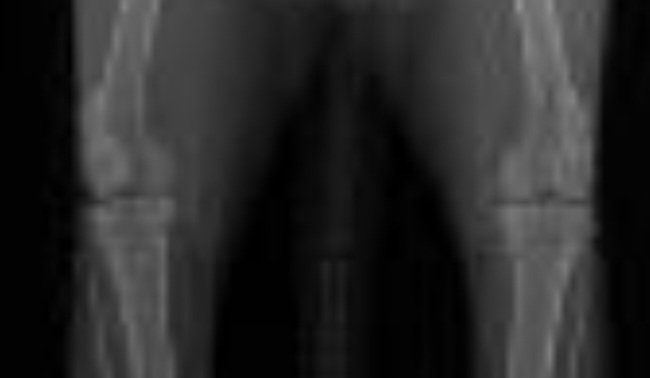

Lynn HD screen 👌

Afbeelding – 161,3 KB

148 downloads

Download